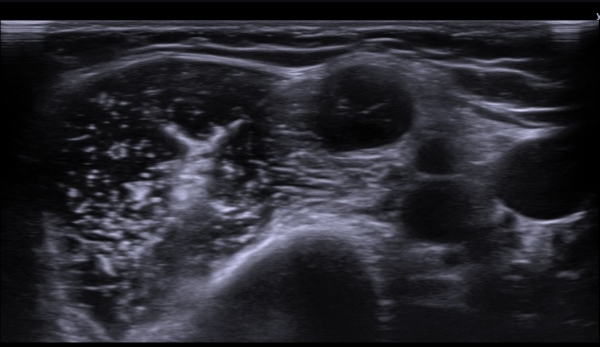

¼â°ñ¾Æ·¡¿¡¼­ »ó¿Ï½Å°æÃÑ Á¾´Ü¸é°Ë»ç¿¡¼­ »ó¿Ï½Å°æÃÑ ¿ÜÃø ²ö(lateral cord)ÀÇ Àú¿¡ÄÚ ºÎÁ¾ÀÌ

°üÂûµÈ´Ù(»çÁø 7).

°æ       °ú : Ÿº´¿ø Àü¿øÇÏ¿© ¾×¿ÍºÎ Á¤Á߽Űæ ÀýÁ¦ ¹× Á¶Á÷°Ë»ç¿¡¼­ ÀüÀ̼º Àӯļ±¾ÏÀ¸·Î Áø´ÜµÊ.